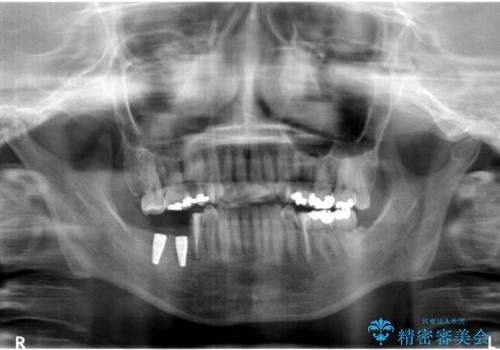

- 奥歯の痛みを主訴に来院された患者様です。

精査したところ、右下の奥歯(右下6)は割れており保存不可能な状態でした。

患者様のご希望により、右下大臼歯2本(右下76)のインプラント治療、右下小臼歯(右下5)の根管治療及び補綴治療を行いました。

割れていた歯の周囲組織の炎症が強く、骨の厚みが薄かったため、インプラント埋入時に骨増生(GBR)を行いました。

インプラントの種類:ストローマン BLT

クラウンの種類:ベレッツァクラウン(右下76)、ジルコニアクラウン スタンダード(右下5)